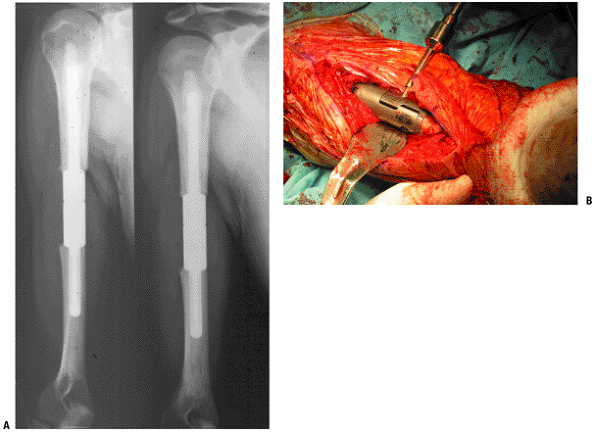

spring device. The expansion procedure does not require a skin incision.P.71![]() Figure 4.3-12 This patient with Ewing sarcoma of the right scapula shown on plain radiograph (A) and T1-weighted (B) and T2-weighted (C) axial magnetic resonance images underwent scapulectomy and prosthetic scapular reconstruction (D), maintaining the integrity of the proximal humeral metaphysis following neoadjuvant chemotherapy.P.72 Figure 4.3-12 This patient with Ewing sarcoma of the right scapula shown on plain radiograph (A) and T1-weighted (B) and T2-weighted (C) axial magnetic resonance images underwent scapulectomy and prosthetic scapular reconstruction (D), maintaining the integrity of the proximal humeral metaphysis following neoadjuvant chemotherapy.P.72 Figure 4.3-13 A proximal humeral osteosarcoma (A) has been reconstructed using an allograft–prosthetic composite reconstruction (B,C). Figure 4.3-13 A proximal humeral osteosarcoma (A) has been reconstructed using an allograft–prosthetic composite reconstruction (B,C).

The intraoperative photo shows dual 90:90 plate fixation of the

allograft and sutures being used to repair the host rotator cuff to the

allograft rotator cuff (C).P.73![]() Figure 4.3-14 This patient with metastatic renal carcinoma to the right proximal humerus (A) Figure 4.3-14 This patient with metastatic renal carcinoma to the right proximal humerus (A)

underwent resection and reconstruction using a proximal humeral

replacement endoprosthesis, shown here intraoperatively prior to

reduction and closure (B).